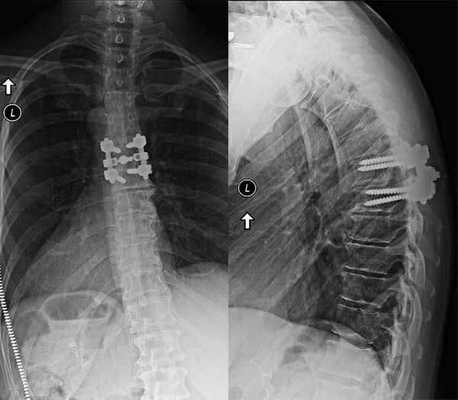

Последний этап транспедикулярной фиксации состоит в создании межтеловой компрессии при помощи специального инструмента и затягивания винтов. На ранее подготовленные декортицированные дуги и поперечные отростки выкладывается алло-или аутотрансплантат. Трансплантат используемый для создания спондилодеза можно смешивать с нативной смесью полученной в результате фильтрации интраоперационного отделяемого во время работы высокоскоростного бора. В конце операции выполняется рентгенологический контроль в 2-х проекциях.

Интраоперационная рентгенография поясничного отдела позвоночника после трансфораминального межтелового спондилодеза.

Сформированный спондилодез на уровне L3-L4.